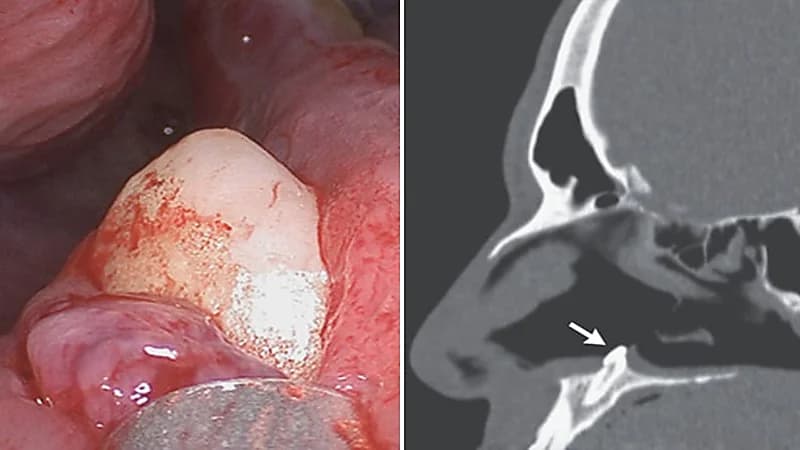

اكتشف جراحون وجود سنًا يبلغ طوله 15 ملم ينمو داخل فتحة أنف رجل أمريكي بعد أن تسبب هذا الأمر بصعوبة كبيرة له في التنفس.

وأجرى الجراحون منظارًا واكتشفوا وجود كتلة بيضاء تظهر من خلال أرضية فتحة الأنف اليمنى ليكتشفوا وجود سن منتبذ يبلغ طوله 15 ملم، والذي يُعرّف بأنه يحتوي على ضرس في مكان غير طبيعي.

وتمكن الأطباء من إزالة الكتلة للمريض عن طريق جراحة داخل الأنف دون أي مضاعفات ما بعد الجراحة.